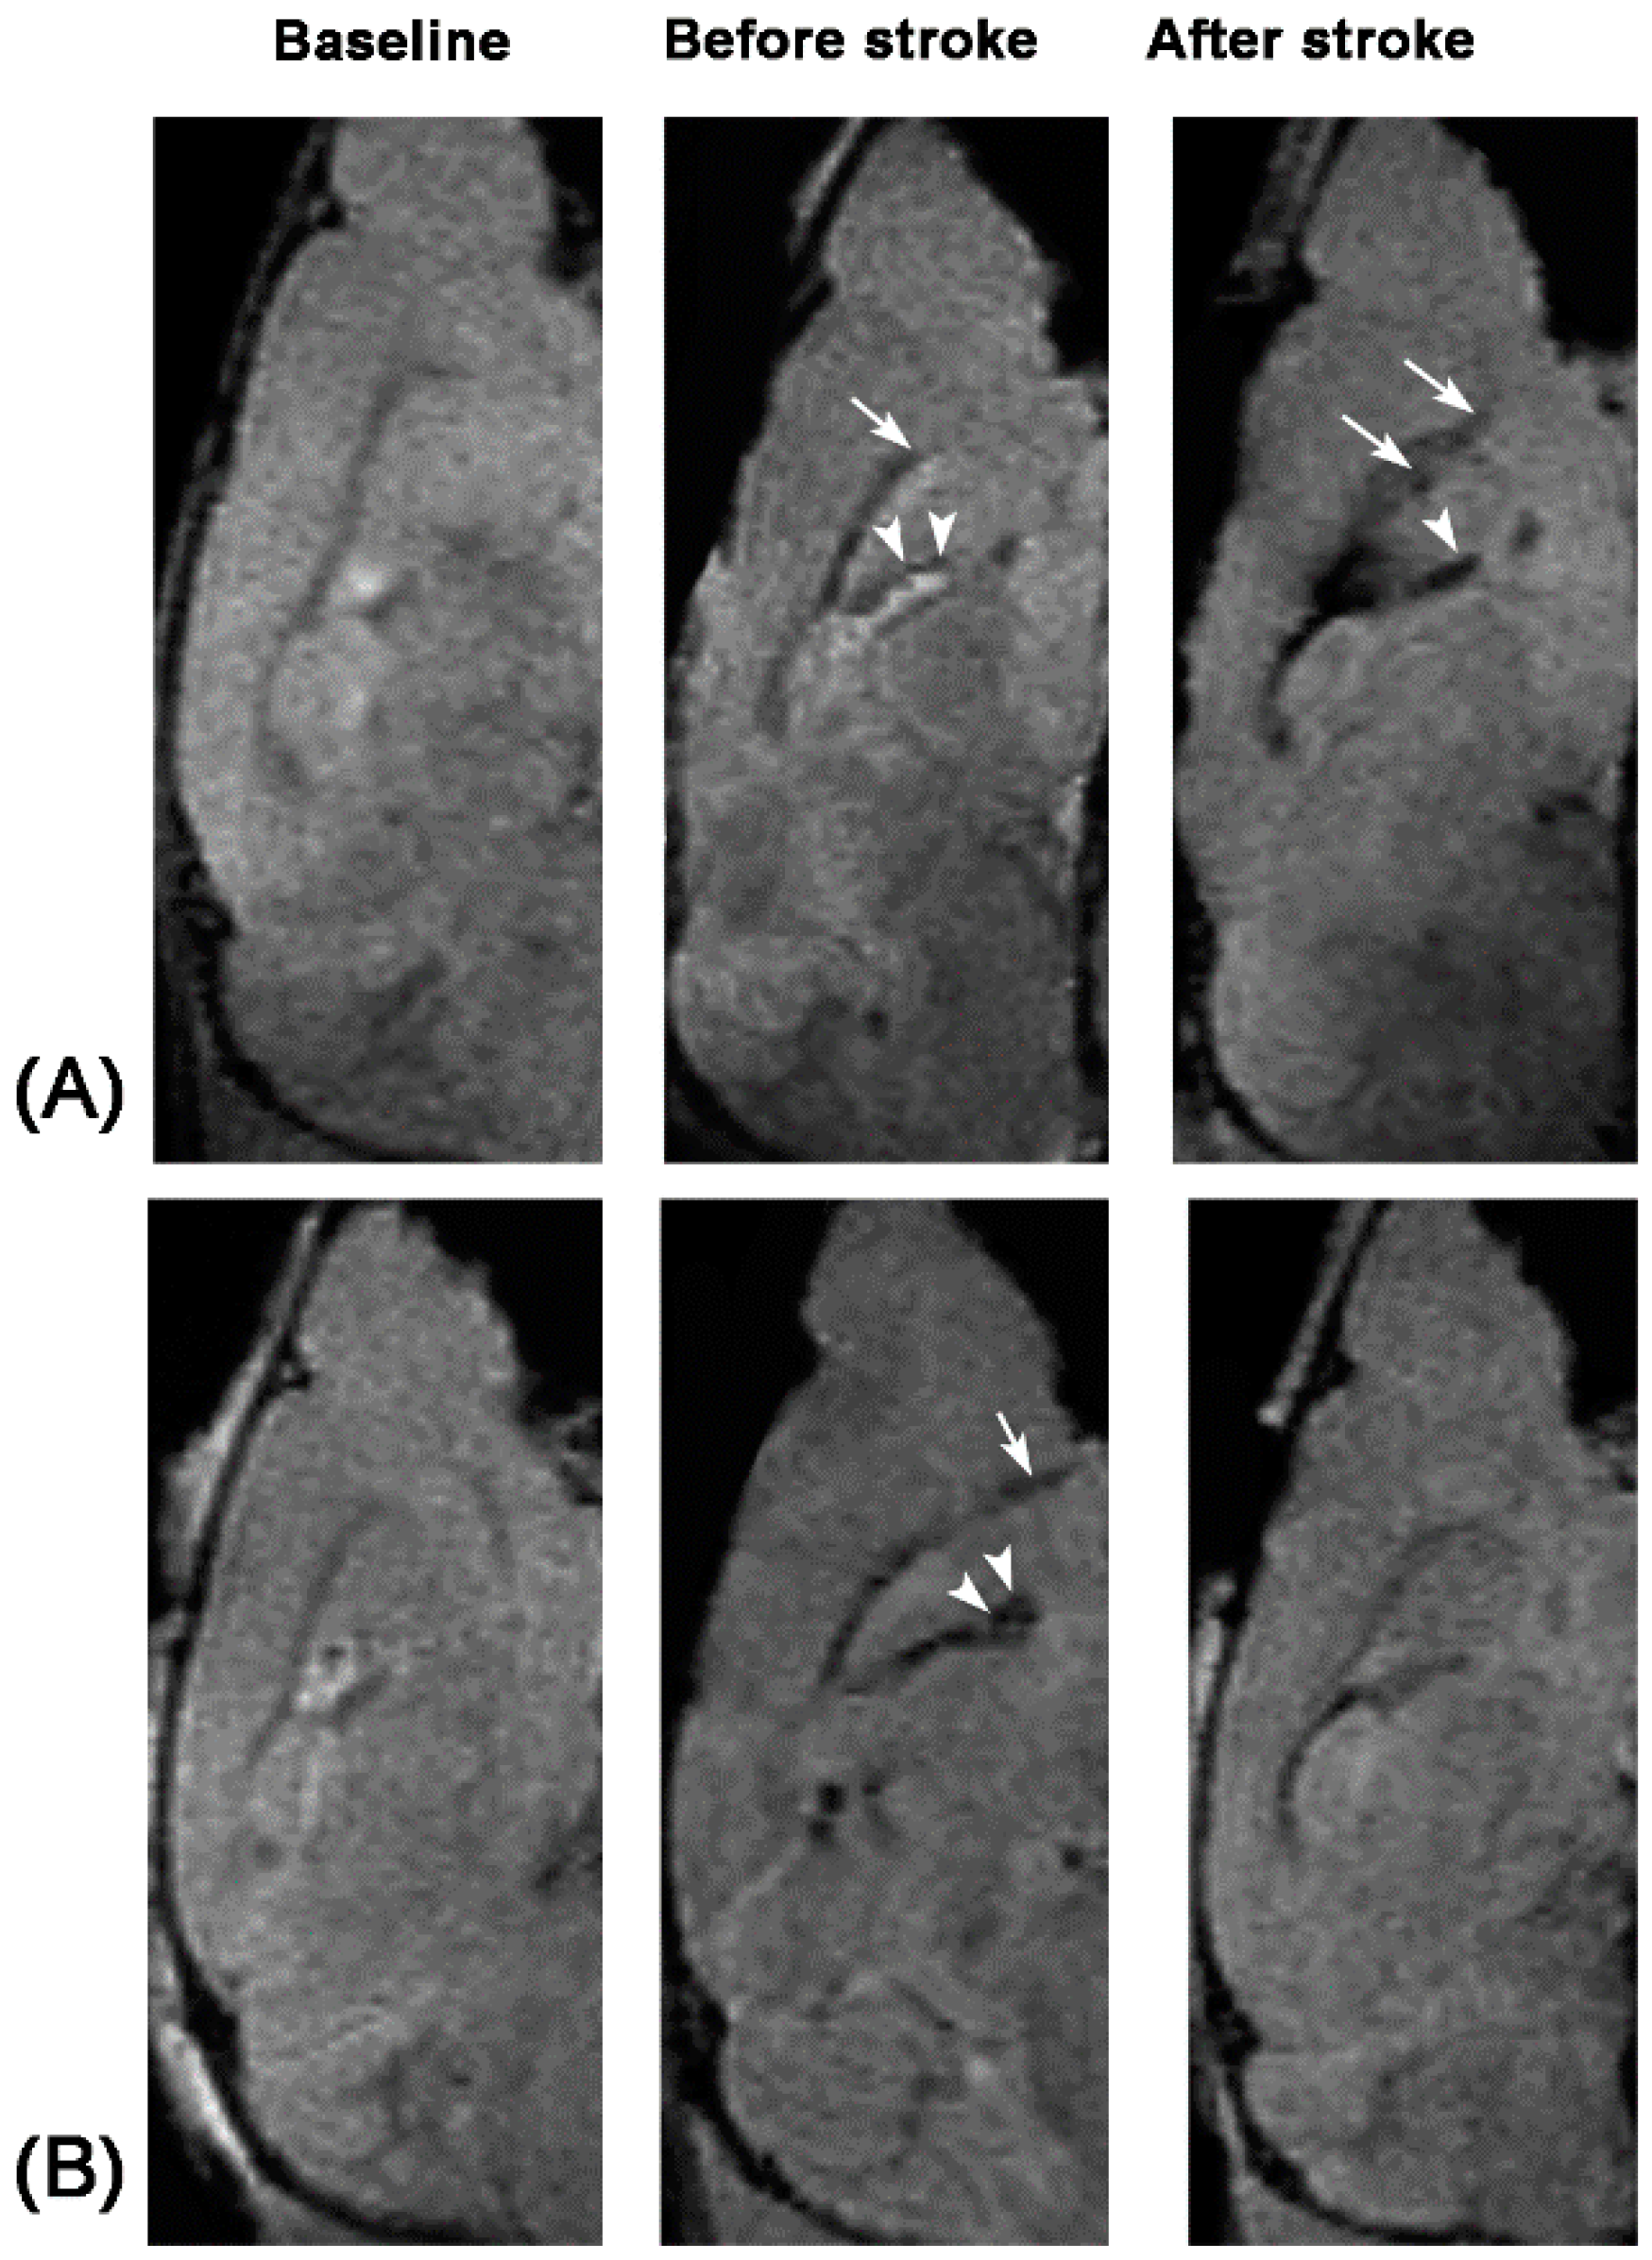

To determine the capacity of in vivo targeted MR imaging of activated NSCs, 12 mice received intraventricular injection of anti-CD15-SPIONs before and seven days after stroke. One day after injection of the imaging probe, the SVZ and the beginning of the RMS were detected as spotty and linear hypointense signals on T2- and T2*-weighted imaging before stroke. Eight days after stroke, these hypointense areas were obviously enlarged (Figure 1A). The volume of hypointense areas was measured before and eight days after stroke. The hypointense volume in SVZ and the beginning of the RMS after eight days of stroke was significantly higher than that before stroke (p < 0.01) (Figure 2).

Figure 1.

Serial in vivo MR images of endogenous NSCs from a pure stroke mouse and a stroke mouse treated with Ara-C. Compared with baseline sagittal T2*-weighted images, after intraventricular injection of anti-CD15-SPIONs, linear hypointense signal (arrows), and spotty hypointense signals (arrowheads) appear in the beginning of RMS and SVZ both in the mouse with pure stroke group (A) and the mouse with Ara-C treatment (B) before induction of stroke. Eight days after stroke, the area of hypointense signal increases in the pure stroke mouse (A), while it diminishes in the stroke mouse treated with Ara-C (B).

2.2. In Vivo MR Imaging of Inhibited NSCs by Ara-C

To further verify the presumption of targeted imaging capacity of anti-CD15-SPIONs, eight stroke mice received intraventricular injection of Ara-C immediately after the establishment of stroke for seven days. Before stroke, the SVZ and the beginning of the RMS in these animals were also detected as spotty and linear hypointense signals on T2- and T2*-weighted imaging. After seven days of Ara-C infusion, hypointense signals in the SVZ and RMS in stroke mice were almost no longer discernable (Figure 1B). The volume of hypoinense signals in the SVZ and the beginning of the RMS on T2- and T2*-weighted imaging were measured before stroke and at eight days after stroke in animals treated with Ara-C. The hypointense volume was significantly lower than that before stroke (p < 0.05) (Figure 2). In addition, the volume of hypointense signal measured before stroke was similar between pure stroke animals and animals treated with Ara-C, while it was significantly lower in stroke animals treated with Ara-C than that in pure stroke animals after eight days following ischemic stroke (p < 0.05) (Figure 2). These findings confirmed the specifically-targeted imaging of NSCs by anti-CD15-SPIONs.